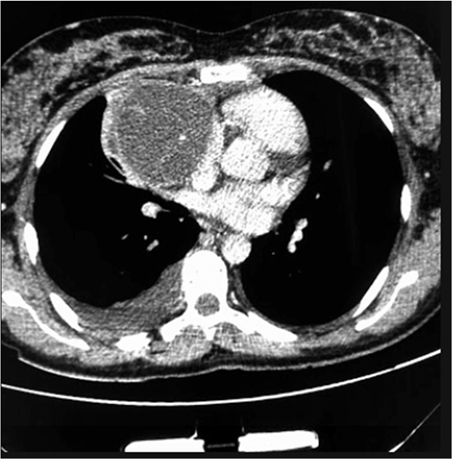

Um paciente de 17 anos de idade revela idas frequentes à emergência por causa de tosse e dispneia. Em exame de imagem investigatório, identificou-se, na tomografia computadorizada de tórax (TCT), uma massa mediastinal anterior bem definida, com densidade de partes moles, medindo cerca de 17 cm x 11 cm x 10 cm, conforme representado na imagem a seguir. A lesão não invadia estruturas adjacentes, e não foram encontradas outras alterações nas tomografias de tórax, de crânio e de abdome. Foi realizada uma biópsia pré-operatória guiada por TCT, cujo diagnóstico foi compatível com teratoma de mediastino.

Considerando esse caso clínico, a imagem apresentada e os conhecimentos médicos correlatos, julgue os itens a seguir.